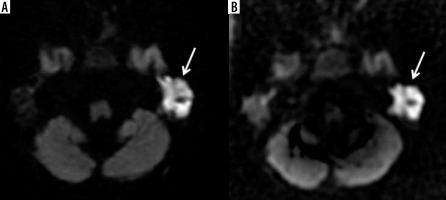

The example of worse diagnostic value of echo-planar imaging (A) compared to non-echo-planar (B) diffusion-weighted imaging in depicting middle ear cholesteatoma (arrows)

The example of no diagnostic value of echo-planar imaging (EPI) (A) compared to non-echo-planar (B) diffusion-weighted imaging (DWI) in depicting middle ear cholesteatoma (arrow). Cholesteatoma in not visible on the EPI DWI image (A) resulting in a false negative result